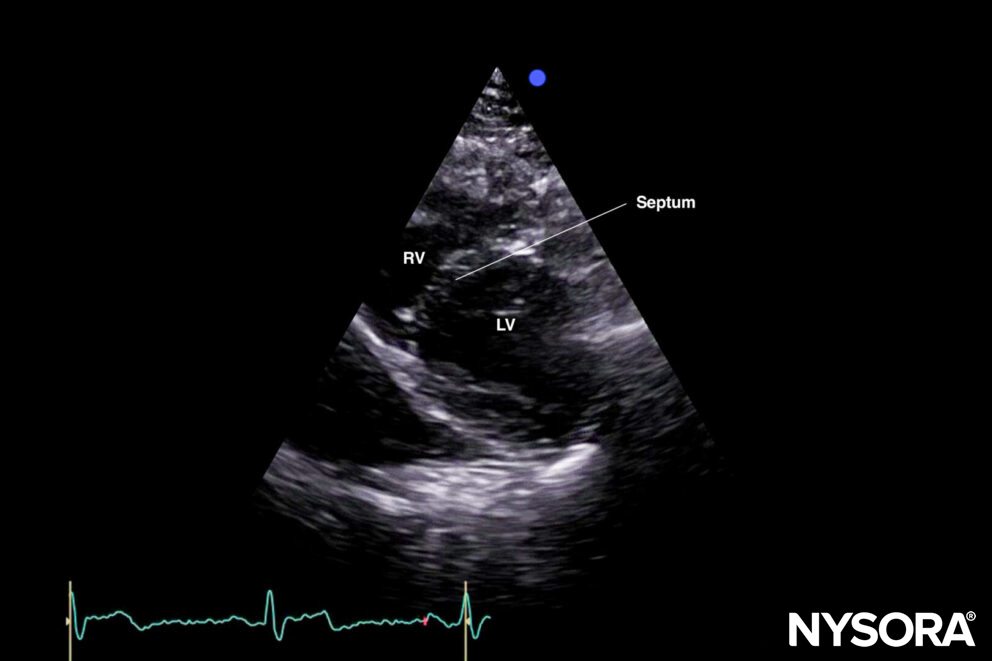

The standard parasternal short-axis view cuts the heart through the transverse plane.

Sonoanatomy of the heart in the parasternal short-axis view. Right ventricle (RV), septum, left ventricle (LV), and papillary muscles.

Reverse ultrasound anatomy:

Reverse Ultrasound Anatomy of the heart in the parasternal short-axis view. Right ventricle (RV), septum, left ventricle (LV), and papillary muscles.